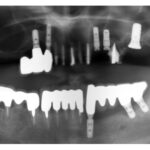

カテゴリー:インプラント

インプラント

インプラントモニター